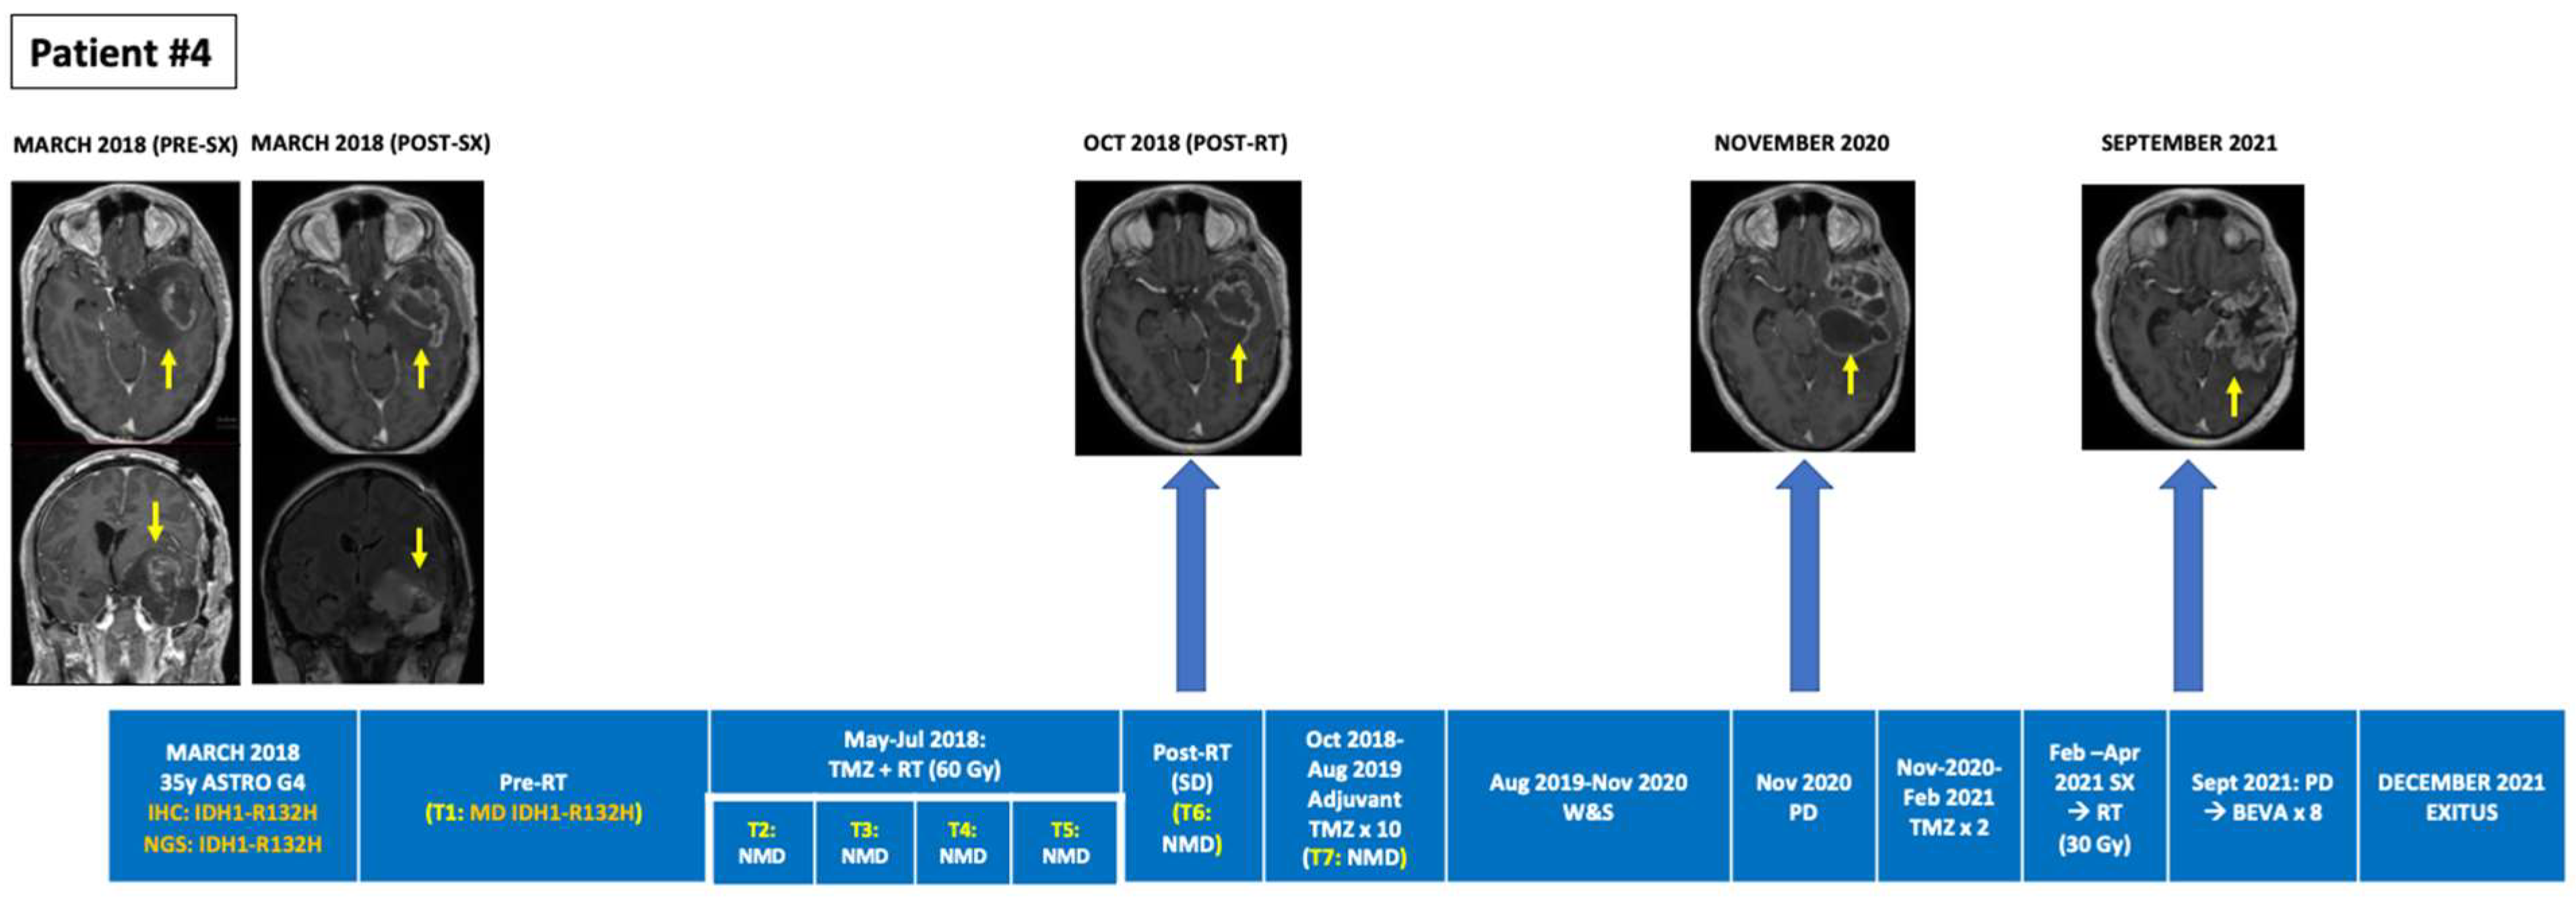

| 4 | Astrocytoma (grade 4), IDH-mutant | 34/ND/SX (PR May 2018)→RT + TMZ→TMZ × 10→W&S (12 m)→TMZ × 2→SX (2021)→RT→PD (Oct 2021)→BEV (ongoing) | 1 | MUT | R132H (31.1%) | R132H (0.377%) (ND; Pre-RT) | NMD (Intra-RT) | NMD (Intra-RT) | NMD (1 m Post-RT) | NMD (2 m Post-RT) | NMD (PsPD; Post 2nd TMZ) | NMD (Post 3rd TMZ) |